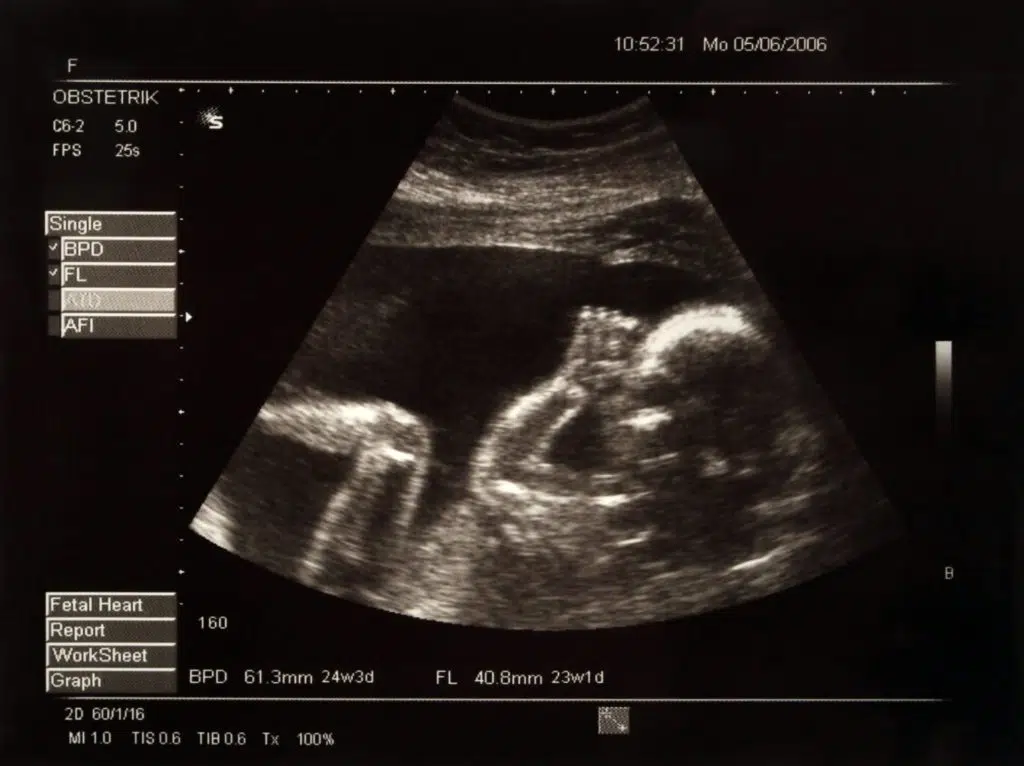

Thanks to advances in neo-natal care, about 10-20% of babies born at 22 weeks – the age of Golob’s baby at the time of the videos – will survive. After 22 weeks, survival rates rise quickly. In other words, the abortionists Golob spoke to had no problem helping her end the life of a preborn child that could easily have survived.

But nobody believes that this is true of the child later in pregnancy. No child in the third trimester can possibly be described as a “blob of tissue.” Nearly everyone by this point has seen late-term ultrasounds.